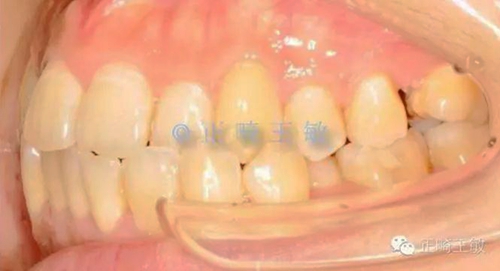

有了一個(gè)目標(biāo)后,矯正就很簡(jiǎn)單了,拔掉一顆牙,7個(gè)月順利讓牙齒移動(dòng)到我們想要的位置:

9.jpg

一年后復(fù)查,沒(méi)有任何問(wèn)題。

11.jpg

只拔了一顆小牙,解決了大問(wèn)題。